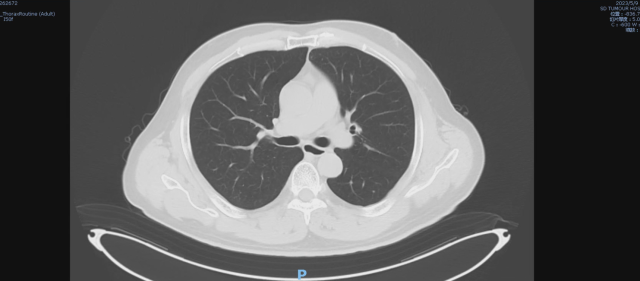

伏罗尼布治疗后,2024-09-09 复查CT

1. 考虑双肺炎症改变,较前范围减小,建议复查

2. 双肺多发结节,较前减小。

3. 双肺多发纤维灶。

4. 心包积液。

5. 肝内多发低密度病变,结合病史,不除外转移瘤可能,较前部分减小:建议必要时 CT 增强扫描进一步检查。

6. 考虑:肝左叶囊肿。